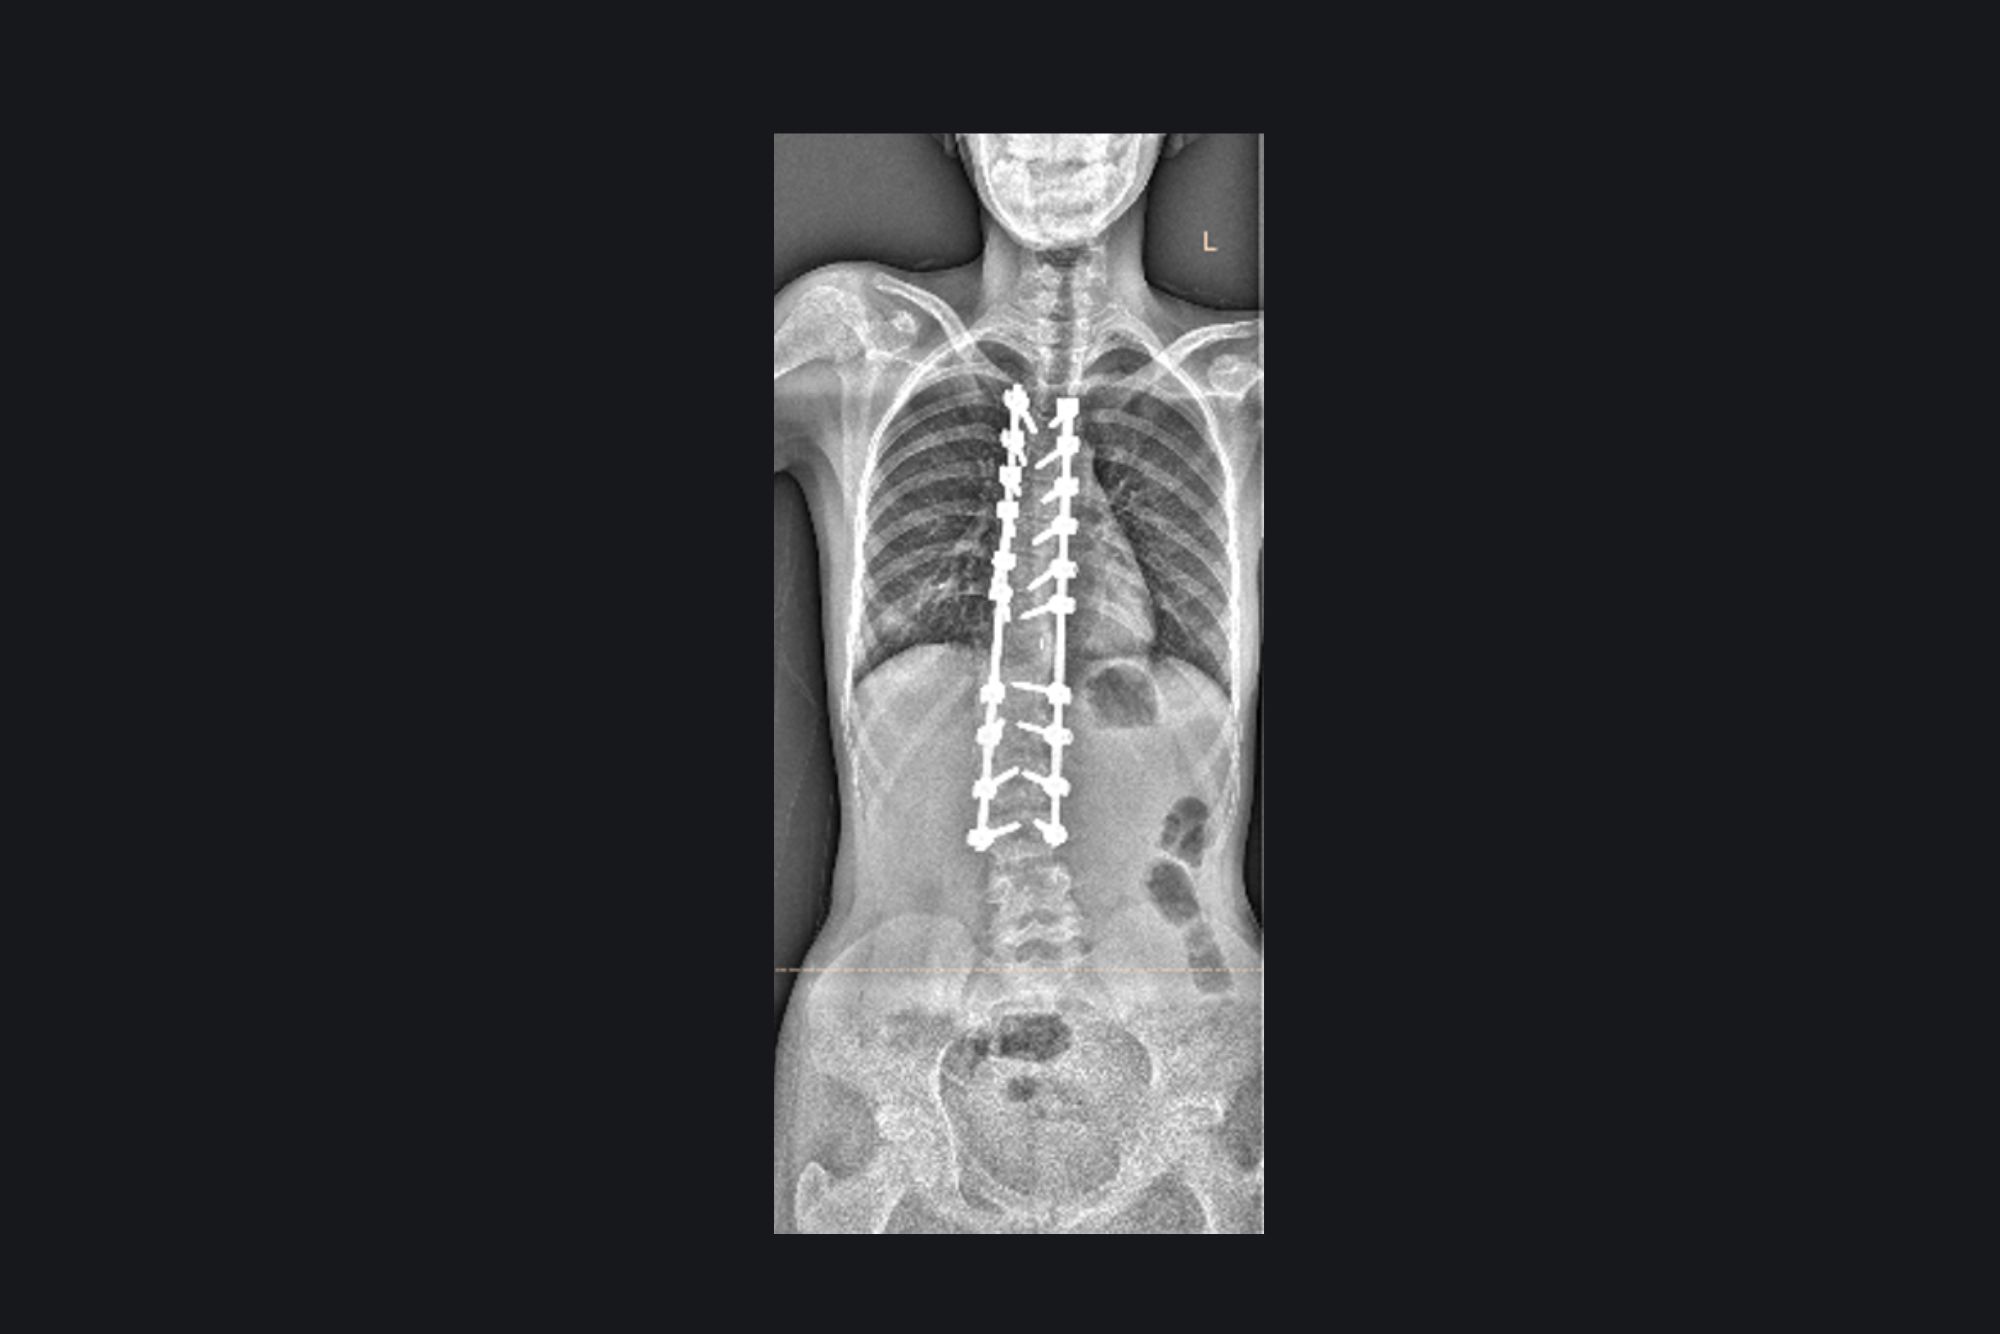

Congenital Scoliosis

PreOperative Image

PostOperative Image